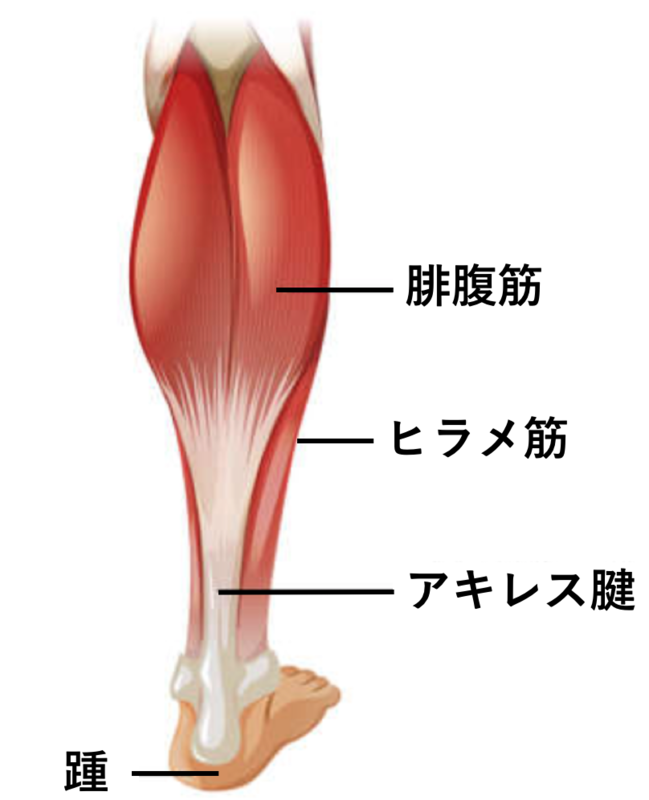

「腱」と呼ばれる組織は全身のいたるところに存在しています。筋肉は骨と骨に付着することで関節の運動を可能にしていますが、「腱」は、この筋肉と骨を繋いでいる組織です。

特に「アキレス腱」は人体の中でも大きな腱であり、ふくらはぎの筋肉である下腿三頭筋と踵の骨を繋いでます。このアキレス腱に負担が生じ、腱に痛みが出る疾患が「アキレス腱炎」です。アキレス腱炎になる危険因子としては、下腿三頭筋の柔軟性低下、足のアライメント不良(例:扁平足)、運動による使いすぎ、肥満などがあり、若年者から中高齢の方まで幅広い年齢層で痛くなるの可能性がある疾患です。